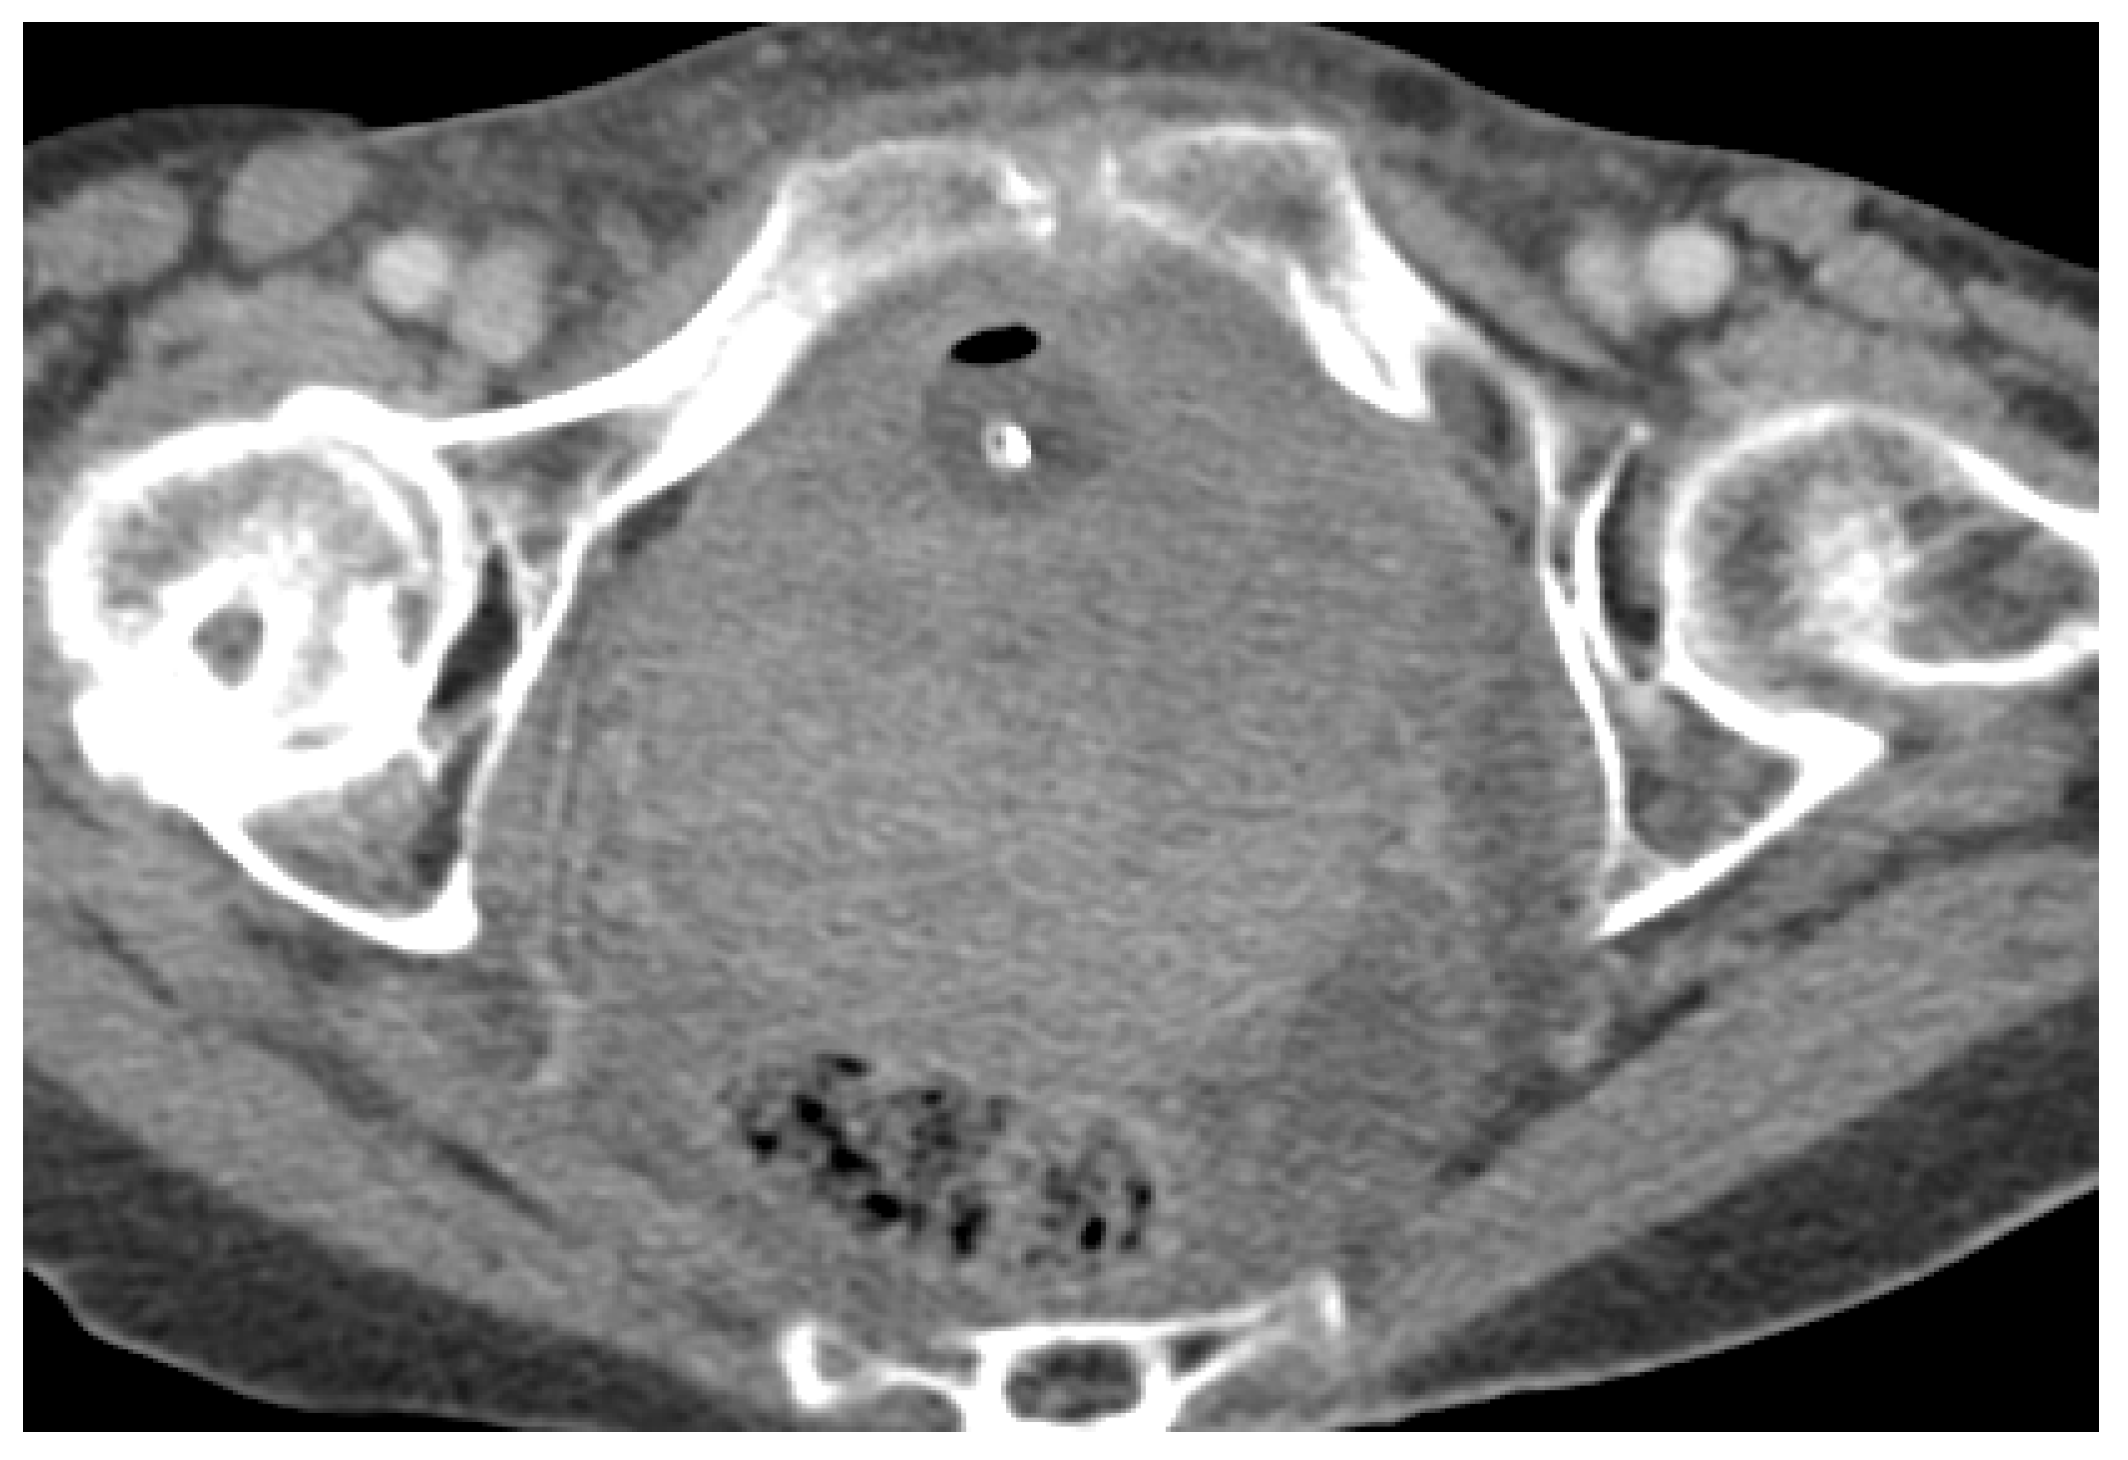

3. Normal Appearance of Urethral Meshes on MRI/CT

4. Urethral Mesh in Oncological Patients